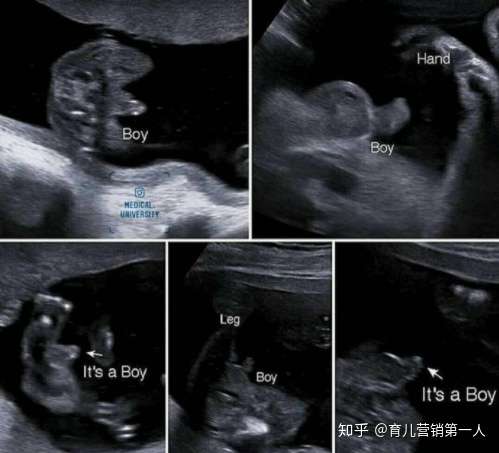

→ cupcook 因為兩次超音波性別結果不同 所以我直接請醫生幫我 01/ 1530 → cupcook 確認當時NINFTY的資料 避免又被翻盤>"< 01/ 1530 推 chinimader 10w醫生說是男生,隔了一週說可能是臍帶在兩腿間目 04/30 1554 因此用超音波來看性別,並不是和大寶寶或是新生兒一樣直接看外型,而是看其「性突起」和身體長軸 (脊椎) 所夾的角度。 這個「性突起」就是將來男性要發育成龜頭、而女性要發育成陰蒂的構造,它和身體所夾的角度越大,是男性的機率就越高。用於量度距離。 通過超音波發射裝置發出超音波,根據接收器接到超音波的時間差就可以知道距離,與雷達測距原理相似。 超音波發射器向某一方向發射超音波,在發射的同時開始計時,超音波在空氣中傳播,途中碰到障礙物就立即返回來,超音波接收器收到反射波就立即停止計時。 (超音波在空氣中的傳播速度為v=340m/s,根據計時器記錄的時間t,就可以計算出發射點

超音波看胎兒性別的真相 王培中 Kingnet國家網路醫藥 Second Opinion

超音波看胎兒性別的真相

14週 16週看寶寶的性別 原來超音波小雞雞長這樣 三個月 四個月其實就可以知道寶寶性別了 J女孩 痞客邦